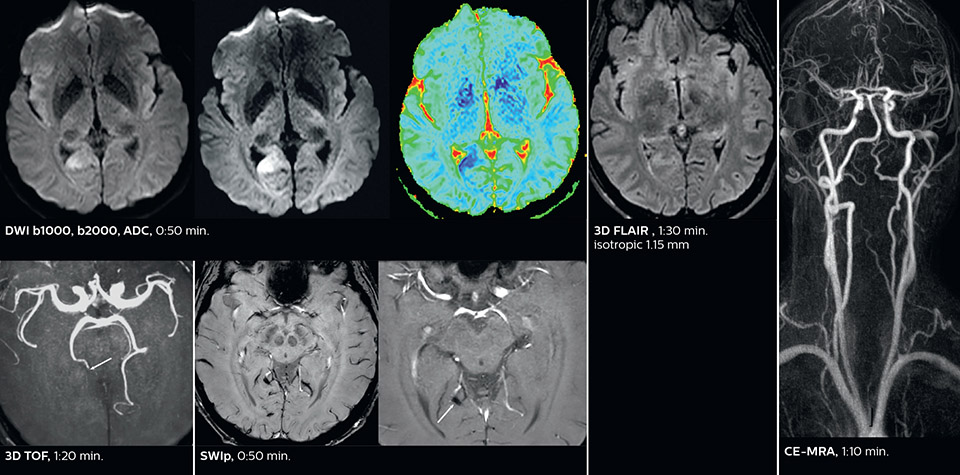

Dr. Savatovsky appreciates the improvements and flexibility that Elition with Compressed SENSE and MultiBand SENSE provides, particularly for stroke patients. “For stroke, it allows us to cut about 5 minutes off of our stroke protocol, or to keep the same acquisition time and get more insights.” The ability to perform more sequences can help in making a swift and confident diagnosis. “For example, our stroke cases usually include the regular sequences that every center does (b1000 diffusion, FLAIR, time-of-flight angiography), but we also image supra aortic vessels, and we can replace a gradient echo sequence with a fast 50-second susceptibility-weighted sequence, and all of this doesn’t add much time. because all the regular sequences are accelerated on Elition.” “The time savings with Compressed SENSE and MultiBand SENSE make it easier to add sequences to give us additional insights. Depending on the context and the first results, we might add a DSC perfusion to assess the ischemic penumbra, an ASL perfusion to help find an alternative cause in case of normal diffusion, or add a high-resolution T1 sequence for a stroke patient, to quickly assess wall imaging in emergency cases. The additional sequences can help improve patient management, because we can already consider some alternative diagnoses if the morphological MRI is normal.”

This is an example of acute ischemic stroke with distal occlusion of the right posterior cerebral artery. Note the improved visibility of the ischemic territory on the diffusion weighted image with high b-value. The 3D FLAIR shows a distal PCA occlusion. The fast SWIp depicts the thrombus on the isolated second echo image. The total scan time (including SmartBrain, preparations and a fast 3D T1w TSE Gd) is 8:00 minutes.